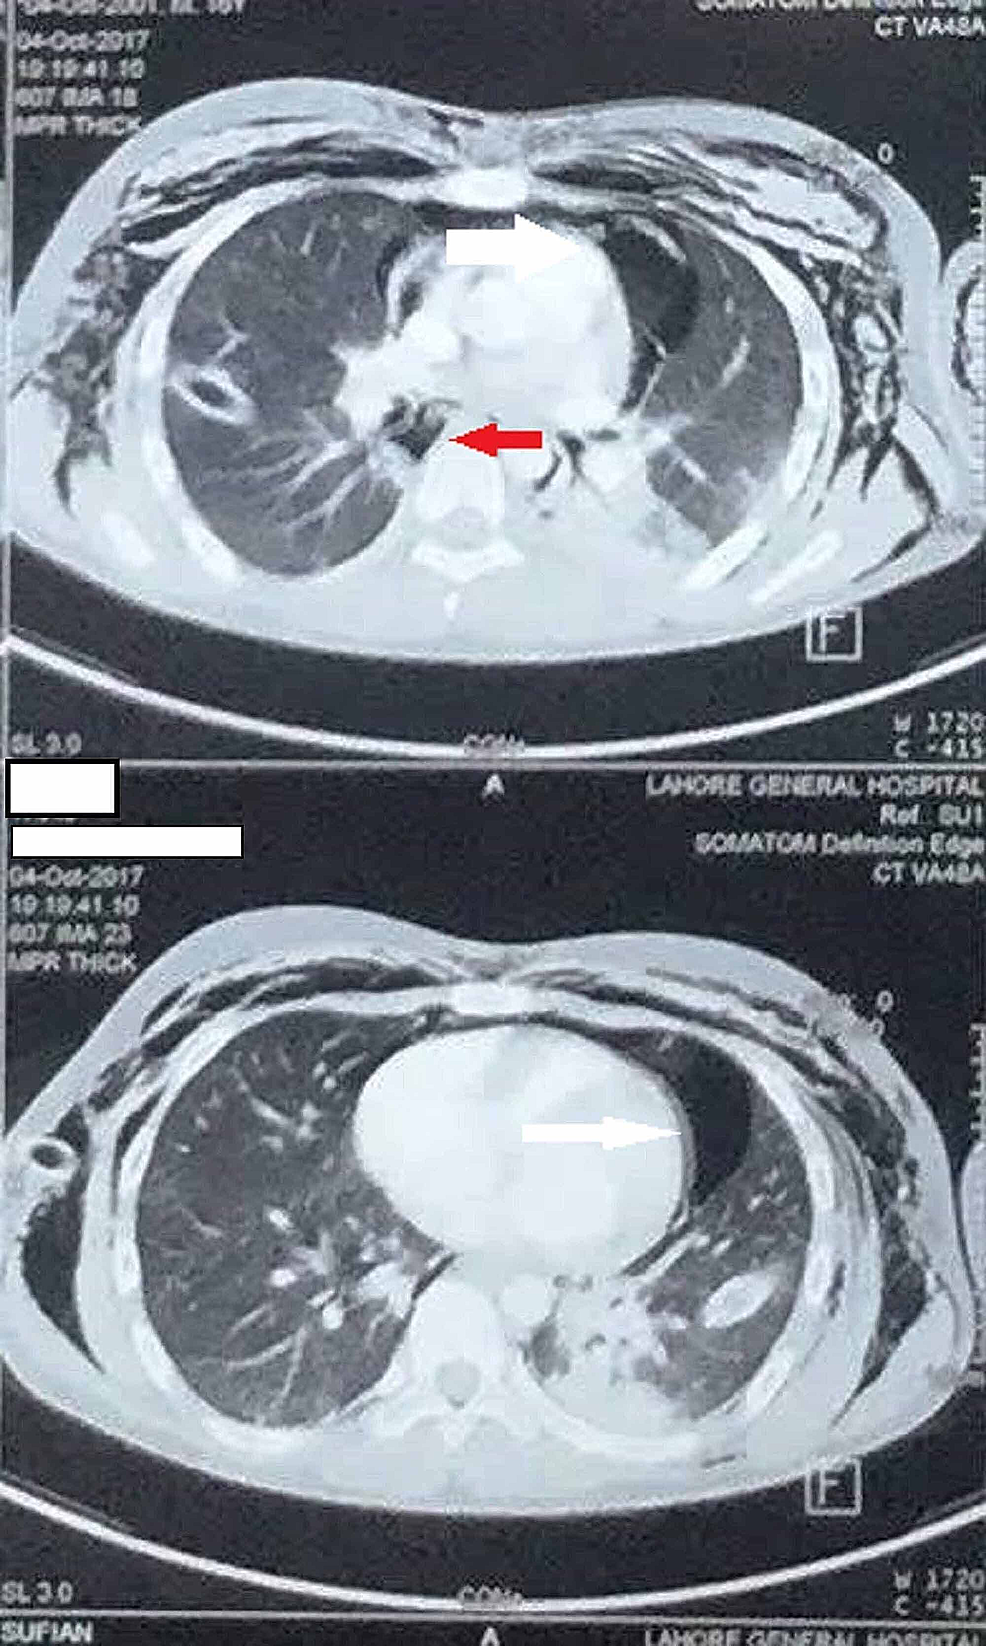

Computed tomography (CT) of the chest was ordered, which showed bilateral pneumothorax with pneumomediastinum (Figure 3).

The classical presentation is usually in patients with a history of varying degrees of shortness of breath, chest pain, difficulty swallowing, and subcutaneous emphysema (crepitation on touch), but our patient came to us with dyspnea. Physical examination of about 30% of patients can be normal in pneumomediastinum [3]. Usually, there may be tachycardia, tachypnea, hyper resonance to percussion, diminished breath sounds, and asymmetrical chest wall expansion may be present on physical examination. Distended neck veins, hypotension or cyanosis, and swelling on the chest radiate to the neck and face mostly due to underlying tension pneumothorax [4]. As in the presented case, the patient is hypotensive, tachycardiac, decreased breath sounds on the right side of the chest initially, and swelling on the chest and neck. However, diagnosis depends on the history and physical examination of the patient but can be confirmed by X-ray, CT of the chest, bronchoscopy for tracheal injuries, esophagoscopy for esophageal lacerations [6]. To make a correct diagnosis, frontal and lateral views of chest radiographs are needed. Accurate interpretation of the chest radiograph is essential in the early diagnosis of the occult upper-airway injury. Radiographic signs of pneumomediastinum on the X-ray of the chest include lucent streaks of gas that outlines mediastinal structures. The reported case was confirmed by X-ray and high-resolution tomography (HRCT) of the chest. Although bronchoscopy and esophagoscopy should be done to rule out any aerodigestive tract injuries, we did not perform it after consultation with a pulmonologist and gastroenterologist due to improvement in patient condition [7]. This is the major limitation in this case report. Whenever bilateral pneumothorax is suspected with pneumomediastinum, initial multidisciplinary evaluation is important for management. Bilateral pneumothorax can be treated according to age, clinical status, and underlying causes. It is usually benign in young patients and can be life-threatening in advanced ages and in patients with limited pulmonary reserve, requiring urgent management. Missed diagnosis and delayed treatment can lead to tension pneumothorax and the patient’s death [8, 9]. Aerodigestive tract injuries can be managed conservatively or by surgery, depending on patients' clinical status [3, 7]. Surgery is recommended for clinically unstable patients, as most patients with major aerodigestive tract injuries undergo primary repair. Pneumonia and mediastinitis prophylaxis should be given to all patients. Our patient became stable with bilateral chest tube thoracotomy and antibiotic cover, and the vitally stable patient was discharged after 10 days.